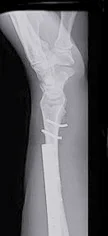

Galeazzi Fracture/ Dislocation

Fracture of the radius with dislocation of the distal radio-ulnar joint

“Fracture of necessity”

- Necessitates surgery

“Fracture of necessity”:

- Plating of radius

- Reduction of distal radio-ulnar joint (+/- Fixation)